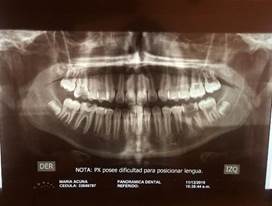

Figura 11, Radiografía periapical a las 8 semanas posteriores Caso 2, no se observa crecimiento alguno de su porción radicular por lo cual se requiere control y seguimiento a largo plazo. (Ver Anexo Figura 12)

Figura 12, segundo control y evaluación radiográfica a los 21 días del molar autotransplantado Caso 2, se pudo evidenciar imagen radiolúcida a nivel del periápice compatible con tejido cicatrizable, observando el tejido óseo como una imagen más densa que el control anterior. Se evidencia reabsorción radicular; se le indicó el próximo control en 30 días para tomar una decisión en cuanto al tratamiento endodóntico. (Ver Anexo Figura 13).

Al realizar el autotrasplante de terceros molares con hemoderivados a los pacientes previamente seleccionados, se obtuvo como resultado que en el estudio de caso 1, el autotrasplante fracasó, debido a que el estadio nolla del tercer molar era 6, no había formación radicular y no se continuó dicha formación. En el estudio de caso 2, se debe seguir realizando el control cada 20 días, ya que en la radiografía periapical se observó la presencia de una ligera reabsorción en la raíz mesial, imagen radiolúcida a nivel apical y a nivel del periápice; al extraer un diente se está destruyendo el periodonto de la zona y las fibras periodontales van a quedar desgarradas y la forma de que esta unidad obtenga estabilidad es mediante la anquilosis ósea. Por ello, se debe seguir en control cada 20 días para determinar si hay que inducir el cierre apical.

Figura 7. Radiografía inicial. (Antes de realizar la exodoncia de las UD 46 y 47 y la implantación de UD48. Caso 2

Figura     11.     Radiografía     periapical     a     los     21     días     del     autotrasplante.

Figura 12. Radiografía pericapical de control del caso 2